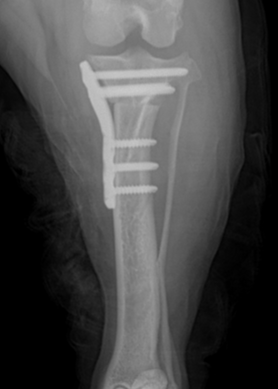

.png)

수술후 방사선 영상

5.예후

수술 후 방사선 평가에서는 수술 전 TPA 30°였던 것이 수술 후 4.7°로 교정되어 목표 범위에 가깝고, tibia의 전반적인 정렬도 계획대로 양호하게 확인되었고 절골면이 서로 잘 맞닿아 있었고, 과도한 틈이나 어긋남 없이 양호한 접촉 상태였습니다.